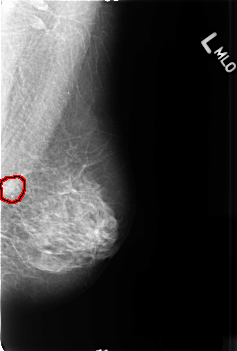

B_3374_1.LEFT_MLO

LEFT_MLO LINES 4560 PIXELS_PER_LINE 3080 BITS_PER_PIXEL 12 RESOLUTION 50 OVERLAY

FILE: B_3374_1.LEFT_MLO.OVERLAY

TOTAL_ABNORMALITIES 1

ABNORMALITY 1

LESION_TYPE CALCIFICATION TYPE PLEOMORPHIC DISTRIBUTION CLUSTERED

LESION_TYPE MASS SHAPE IRREGULAR MARGINS ILL_DEFINED

ASSESSMENT 4

SUBTLETY 4

PATHOLOGY MALIGNANT

TOTAL_OUTLINES 1

BOUNDARY